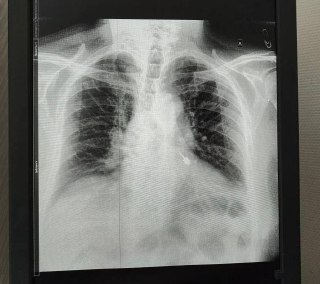

При диагностике медики обнаружили инструмент в левом бронхе.

«Ситуация требовала срочную операцию: любое промедление могло привести к серьёзным осложнениям, вплоть до летального исхода. Главная задача заключалась не просто в удалении инородного тела, а в том, чтобы сделать это максимально аккуратно: острая часть бура могла повредить стенки бронха, вызвав кровотечение или перфорацию. Специальным эндоскопическим инструментом бур был надёжно зафиксирован и плавно извлечён — без травмирования окружающих тканей», — рассказала врач-эндоскопист Мария Юрченко.